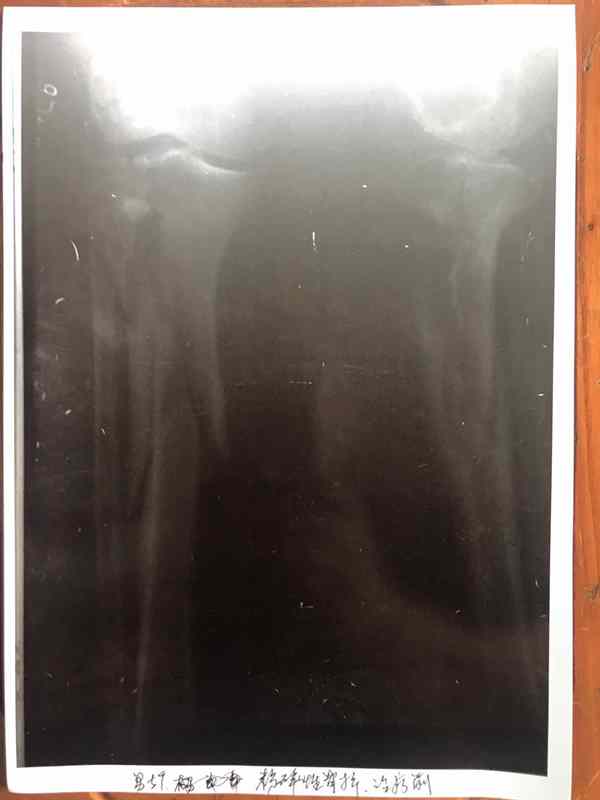

2、非手术治疗:骨结核,股骨头坏死,骨伤后,骨质不长,《骨细胞可快速生长》。目前在医学界还没有发现治疗骨病这种速度,请看下面图片检查结果对比。颈椎病引起的头昏,头痛、腰椎病,腰椎手术后遗症,一至2天见效。